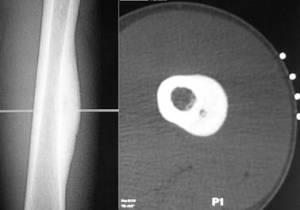

|

Остеоидная остеома |

Вид новообразования, который встречается примерно в 10% случаев всех опухолей позвоночного столба. Плохо диагностируется при рентгене, но четко определяется с помощью КТ и МРТ, хорошо поддается лечению и редко рецидивирует. |

Остеобластома |

Разновидность остеоидной остеомы, которая не вырастает более чем на 2 см, локализуется на задней части позвонков, обладает достаточно ярко выраженной симптоматикой и имеет склонность к появлению на тот самом месте. |

Остеобластома позвоночника